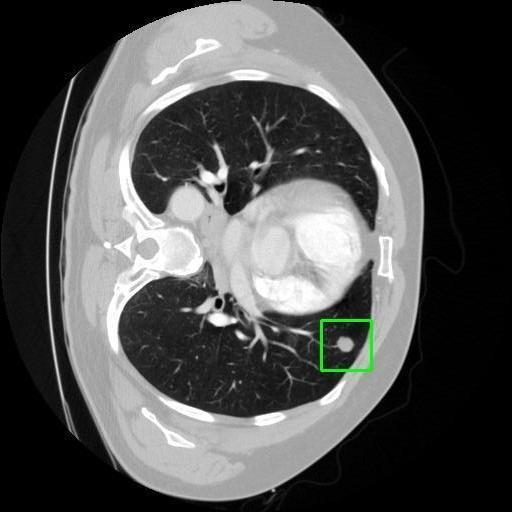

We developed an AI-based system using deep learning models for analyzing lung CT scans to detect and classify pulmonary nodules. We chose the YOLOv11 architecture for its enhanced object detection capability and adapted it specifically for medical imaging, incorporating pixel-level precision and severity classification.

Classification into three severity levels with colored bounding boxes.

Designed a severity classification system that categorizes nodules into null, moderate, and severe using colored bounding boxes, assisting in rapid clinical decision-making.